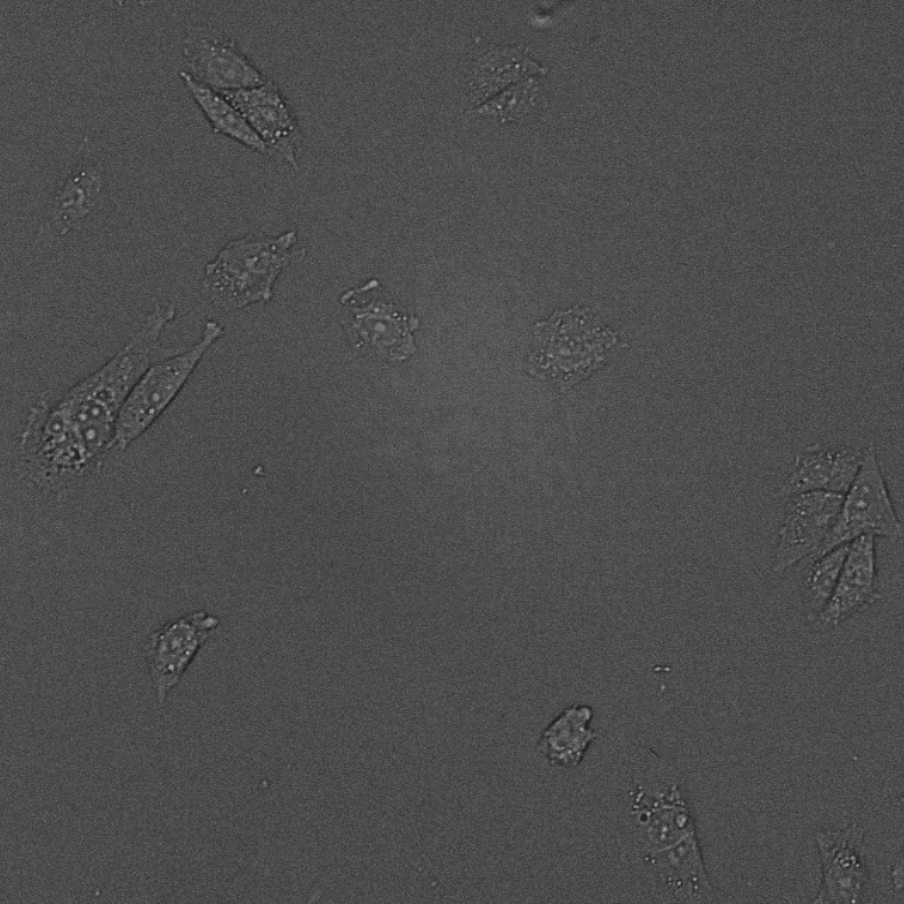

We process images of all kinds. As for medical imaging both structural and functional modalities like MRI, CT, PET, UH and X-ray are supported. Microscopy imaging for laboratory purposes offered in our portfolio include histopathology (H&E, IHC), cytology (e.g. pap smear), blood smear, cell culture and fertility/IVF. Regarding research we create solutions for brightfield and fluorescent microscopy, high-content screening, pharmaceutical testing, bacteria colony counting etc.

We develop state-of-the-art AI solutions for the automatic segmentation (e.g. tissue region, single cell), object detection (e.g. target cell, bacteria), classification (e.g. healthy vs malignant), tracking (e.g. movement) and progress monitoring (e.g. cell growth, confluence) of images.